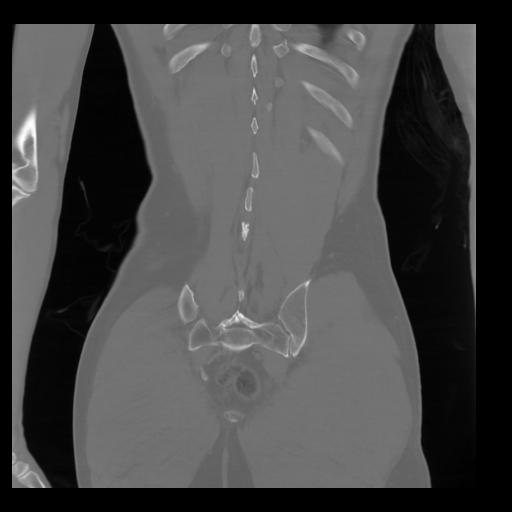

35 CUERPO,CE,Coronal,3.000,CUERPO,Coronal,